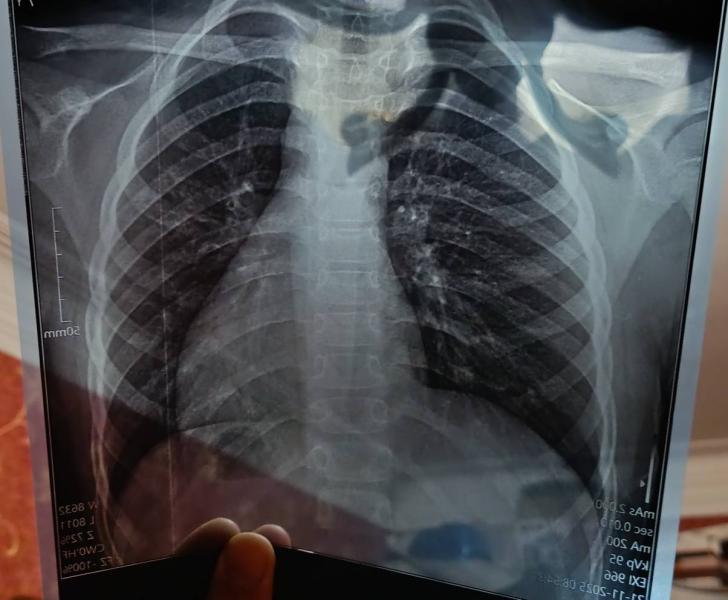

Как думаете есть пневмония или нет 🤔🤔🤔?

@djducnrueic18373, сказал что снимок затенен чем-то. Как будто неправильно сделали

Есть 90%, легочный рисунок усилен